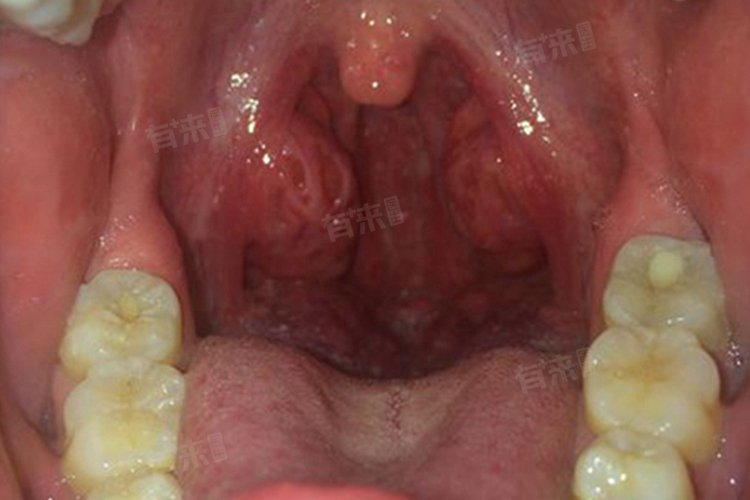

喉咙两边肿大可能会出现多种症状,包括外观肿胀、吞咽不适、声音变化、呼吸困难等。如果发现喉咙两边肿大,应及时就医,明确病因并进行相应的治疗,同时要注意日常的护理和观察,避免病情加重。

1、外观可见的肿胀:轻度的喉咙两边肿大可能在外观上并不十分明显,但仔细观察可以发现颈部两侧稍有隆起。随着肿大程度的加重,颈部的肿胀会越来越明显,甚至可以看到明显的肿块突出。在严重的情况下,可能会导致颈部变形,影响外观。

2、吞咽不适感:喉咙两边肿大往往会对吞咽功能产生影响。患者在吞咽食物或唾液时,可能会感觉到有异物感、梗阻感或疼痛。这种吞咽不适感的程度会随着肿大的加重而增加,轻度肿大时可能只是在吞咽某些较大或较硬的食物时才有感觉,而严重肿大时,即使是吞咽流质食物也会感到困难。